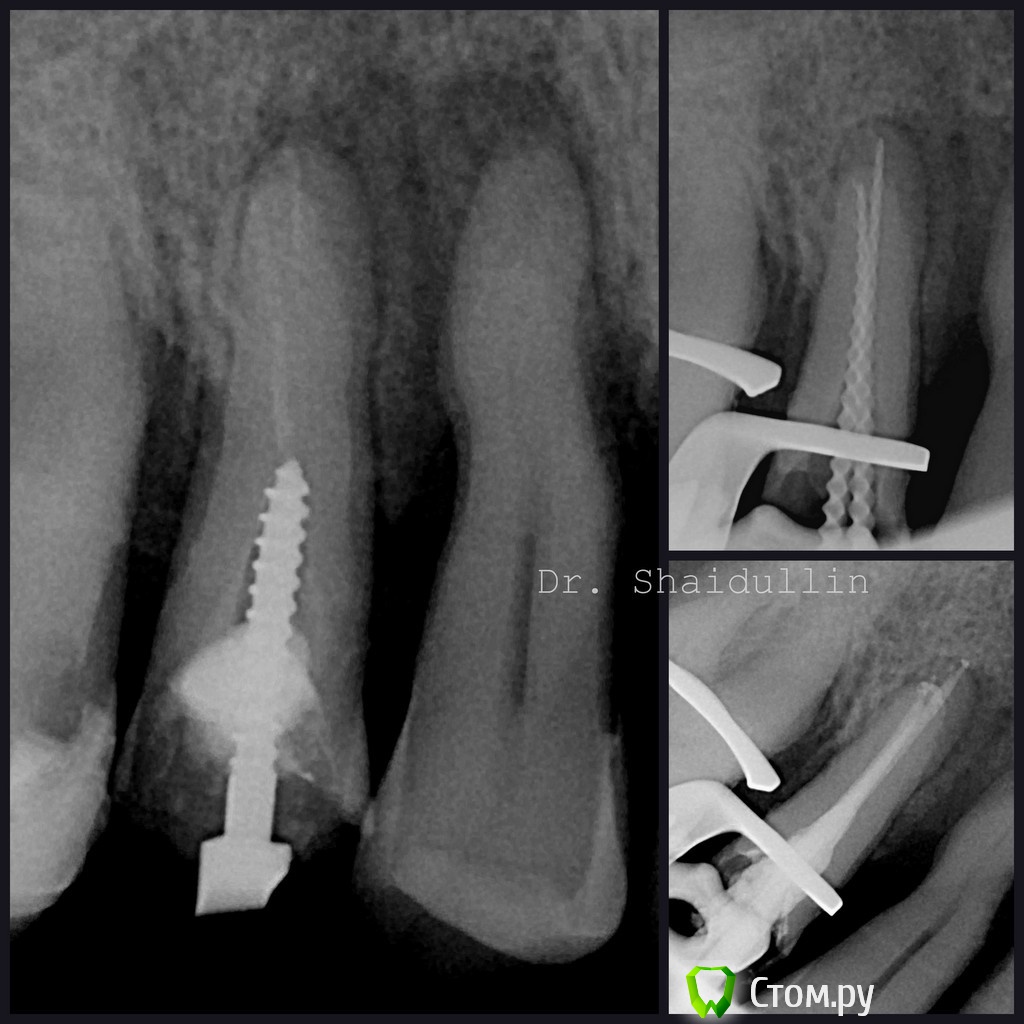

Shaid Опубликовано 3 июня, 2014 Автор Поделиться Опубликовано 3 июня, 2014 Люблю, когда в латерали затекает 6 Ссылка на комментарий

Shaid Опубликовано 18 августа, 2014 Автор Поделиться Опубликовано 18 августа, 2014 Два симметричных зуба(43,33) одного пациента, обрабатывались одинаково. Непредсказуемый Guttacore ногами не бить 1 Ссылка на комментарий

Гарриевич Опубликовано 19 августа, 2014 Поделиться Опубликовано 19 августа, 2014 на калибровочном снимке же видно, что у 33 (который справа на фотке) апекс раструбом, поэтому гутта/силер и вышли. в таких случаях надо рабочую уменьшать до расширения и кор сувать на 0,5 мм меньше)кстати что странно, когда его только в клинику привезли, раз 5-6 он(или только силер, не знаю) у меня выскакивал за апекс и ни каких болей ни во время ни после Ссылка на комментарий